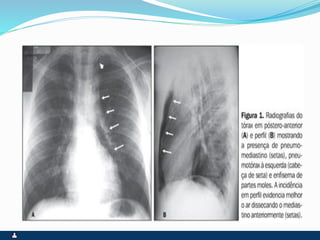

PNEUMOTÓRAX

RUPTURA DE UM DOS FOLHETOS

SINTOMAS SINAIS

 PRIMÁRIO ( ESPONTÂNEO

) SECUNDÁRIO(

TRAUMA,IATROGÊNICO )

 INÍCIO SÚBITO

 DOR PLEURÍCA INTENSA

 TOSSE SECA

 DISPNÉIA

 FACIES DE DOENÇA

AGUDA,ANSIEDADE E

SUDORESE

 EXPANSIBILIDADE REDUZIDA

 DESVIO CONTRALATERAL DO

MEDIASTINO

 ABAULAMENTO

HOMOLATERAL DOS

ESPAÇOS INTERCOSTAIS

 FTV ABOLIDO

 TIMPANISMO

 MV ABOLIDO

 RUIDOS ADVENTÍCIOS

AUSENTES

 ENFISEMA SUBCUTÂNEO

EVENTUAL

ENFISEMA SUBCUTÂNEO